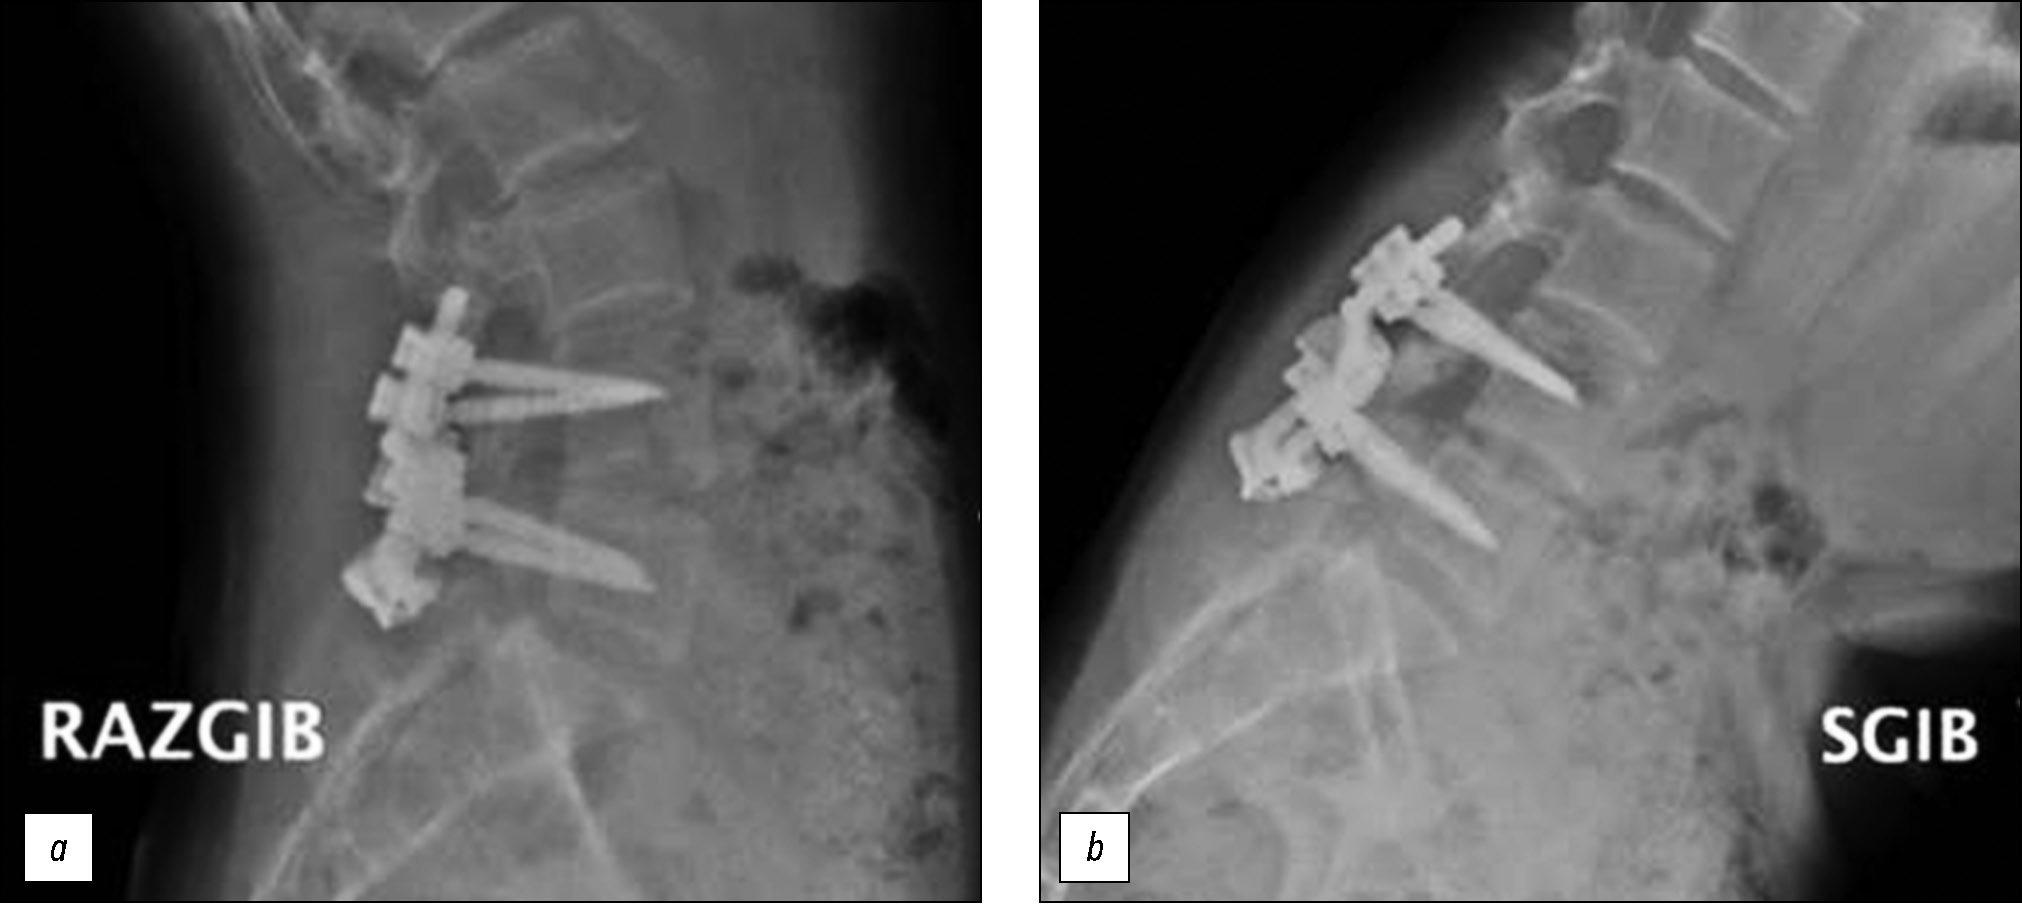

Через три месяца с момента операции пациент полностью восстановил объём физических нагрузок. Болевых ощущений в поясничном отделе позвоночника не отмечает (Ped`s QL — 96 баллов, VAS — 0 баллов). По данным функциональной рентгенографии поясничного отдела позвоночника — положение имплантатов корректное, фиксация стабильная, движения в позвоночно-двигательных сегментах, на которых проводилось оперативное вмешательство, сохранены (рис. 8).

Рис. 8. Функциональная рентгенография поясничного отдела позвоночника: a — положение разгибания, b — положение сгибания.

Fig. 8. Functional radiograph of the lumbar spine: a — extension position, b — flexion position.